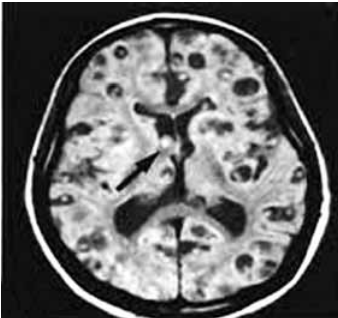

Analise a imagem de um paciente com diagnóstico de epilepsia e assinale a alternativa correta referente às neuroparasitoses mais comuns no Brasil.

(https://www.google.com/imgres?imgurl=x-raw-image)